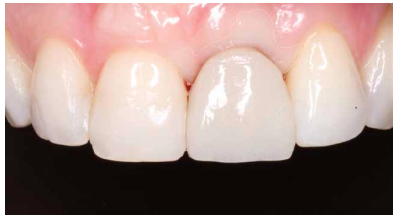

A los 6 meses se puede observar una correcta disposición de los tejidos blandos, así como la estabilidad de estos en el tiempo debido al manejo de los mismos a través de la prótesis provisional (Figura 24). Se realizó además un control radiológico para conocer el estado de los tejidos duros (Figura 25).

Dada la correcta evolución del caso a los 6 meses, se llevó a cabo el registro de la posición del IOI y del perfil de emergencia mediante un transfer individualizado con el fin de replicar de forma fiel y detallada la arquitectura gingival (Figuras 26 y 27). Finalmente se colocó la prótesis fija final atornillada al IOI a los 7 meses del inicio del tratamiento (Figuras 28 y 29).